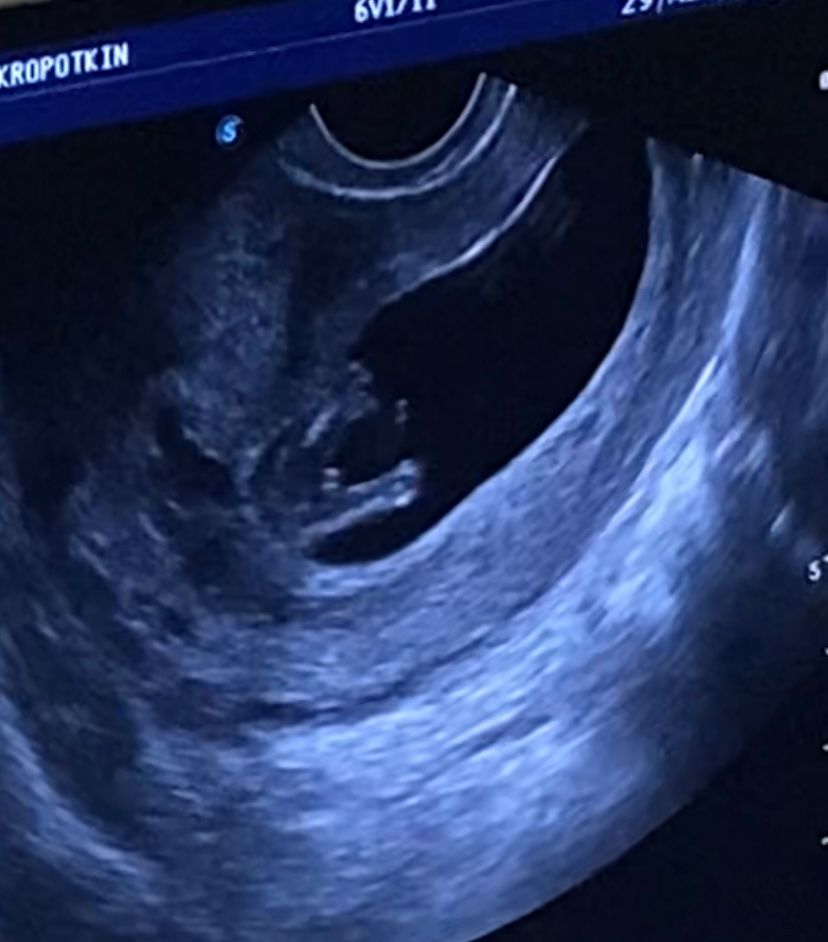

Отгадываем пол в 12 недель

Качество узи плоховастенькое) Сложно понять или сказать 😃 Мне кажется девочка)))

Виктория, первая фотка это между ног вид😅 вторая фотка это вид сбоку, животик

Анастасия, аааа..ну вот там,где между ног,мне кажется мальчик,т.к мошонка вроде бы и она не ровно,как у девочки была бы пися,а вбок😀 ну это может моя фантазия😂 но ставлю,что у вас пацан)))

Мне УЗИст сказал что снизу не смотрят. А сбоку ножки согнуты бугорок не виден. Сложно опровергнуть.

Мальчик либо клитор увеличен так тоже бывает

Мальчик вроде

похоже на мальчика, да